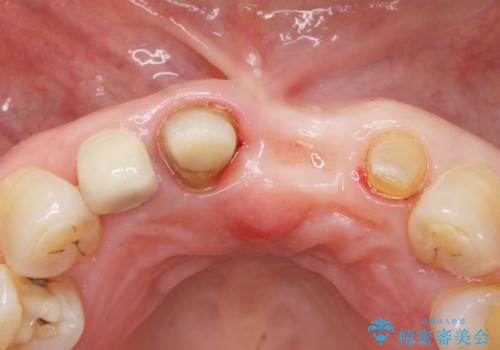

抜歯後歯肉の治癒を十分に待ったのち、ブリッジによる補綴治療を行いました。

歯周病が重度であったため抜歯後の歯肉の陥凹が大きく、GBRや歯肉移植による歯周組織の再建をおすすめしましたが、ご希望されませんでした。

上の前歯の再根管治療もおすすめしましたが、必要性を感じないとのことで土台のやりかえだけをご希望されました。